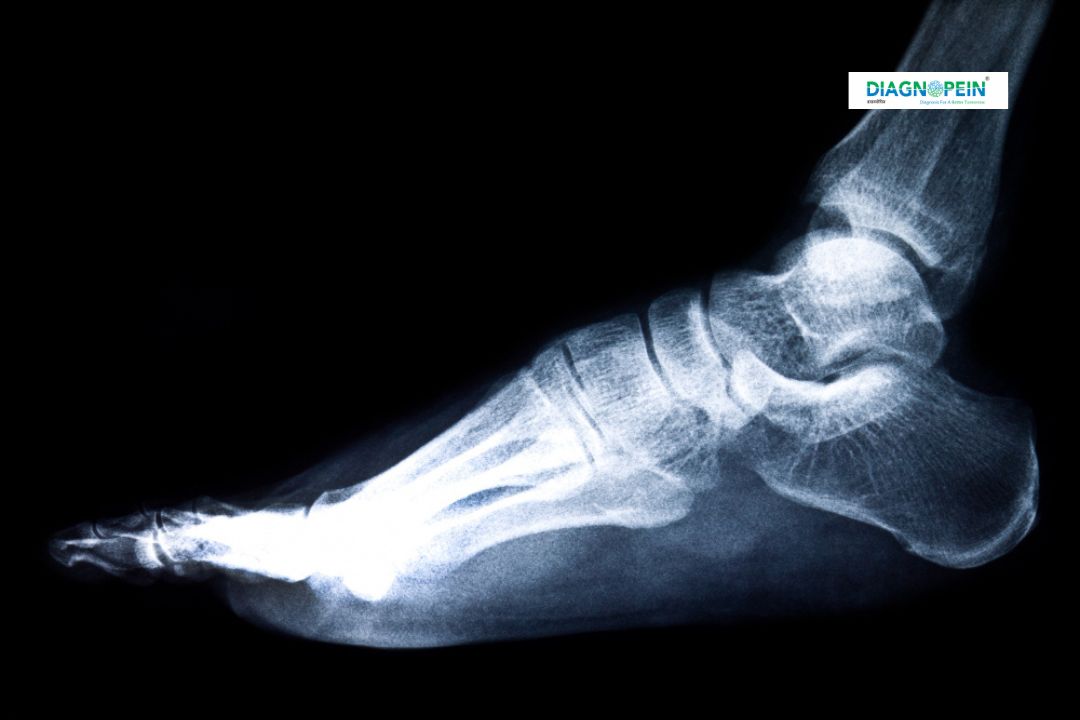

The X-Ray Both Heels Lateral test is a specialized diagnostic imaging procedure used to capture detailed side views of both heels. This test plays a major role in evaluating bone alignment, detecting fractures, and identifying abnormalities in the heel bones (calcaneus). At Diagnopein in Karad, our advanced X-ray imaging technology ensures precise and high-quality results for accurate diagnosis. The procedure is safe, quick, and painless, making it suitable for patients of all ages.

The X-Ray Both Heels Lateral test provides clear, detailed side-view images of both heels together. This helps in identifying even the smallest bone injuries or growths that might go unnoticed. It is often an essential diagnostic tool before surgery or further treatment planning.